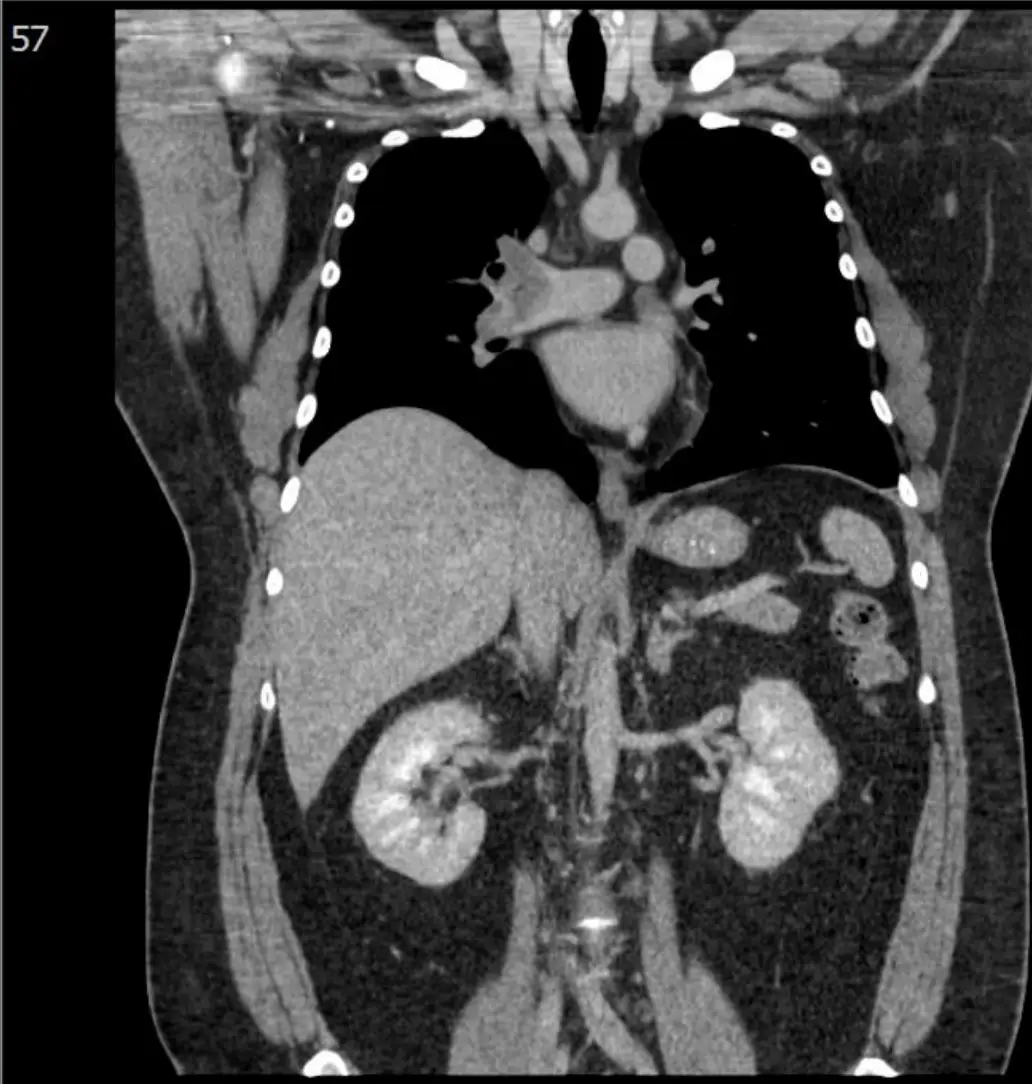

40歲企業主管因有心悸及呼吸困難有一個星期之久,乃前往A院求診,認定是上呼吸道感染,但處置無效,三天後至B院。病人在2009年診斷突發性上心室快跳,且有多年肥胖(BMI=41.5 Kg/m²) 。理學檢查: BP: 156/91 mmHg, HR:141/min, RR:28/min, Temp: 36.90℃, SpO2: 97%,無貧血,頸靜脈正常,甲狀 腺未有異常,胸部有混濁呼吸聲,心臟稍大,不正常律動,未有S3及心雜音,肝脾不大,無腹水,雙下 肢微腫時,心電圖、胸部X-光及胸部電腦斷層如圖。其生化及血液氣體檢驗如表。請問下列何項診斷最 正確? 圖片描述 圖片描述 圖片描述 圖片描述 圖片描述

急性肺動脈栓塞 (pulmonary embolism, PE) 所引起的右心負荷急劇上升,可在心電圖、動脈血氣與 NT-proBNP 等檢查呈現「右心受壓」表徵,影像學上最具決定性的證據為 CT pulmonary angiography 內之肺動脈充盈缺損。本題即圍繞此「急性右心負荷+肺動脈內血栓」的鑑別診斷。

影像分析:

3. 胸部 CT (axial 與 coronal)

• 主肺動脈及左右肺動脈幹可見低密度充盈缺損被對比劑包圍,呈「中央栓子」樣 (central filling defect)。

• 右心室略大於左心室,肺動脈主幹直徑增大,皆為急性右